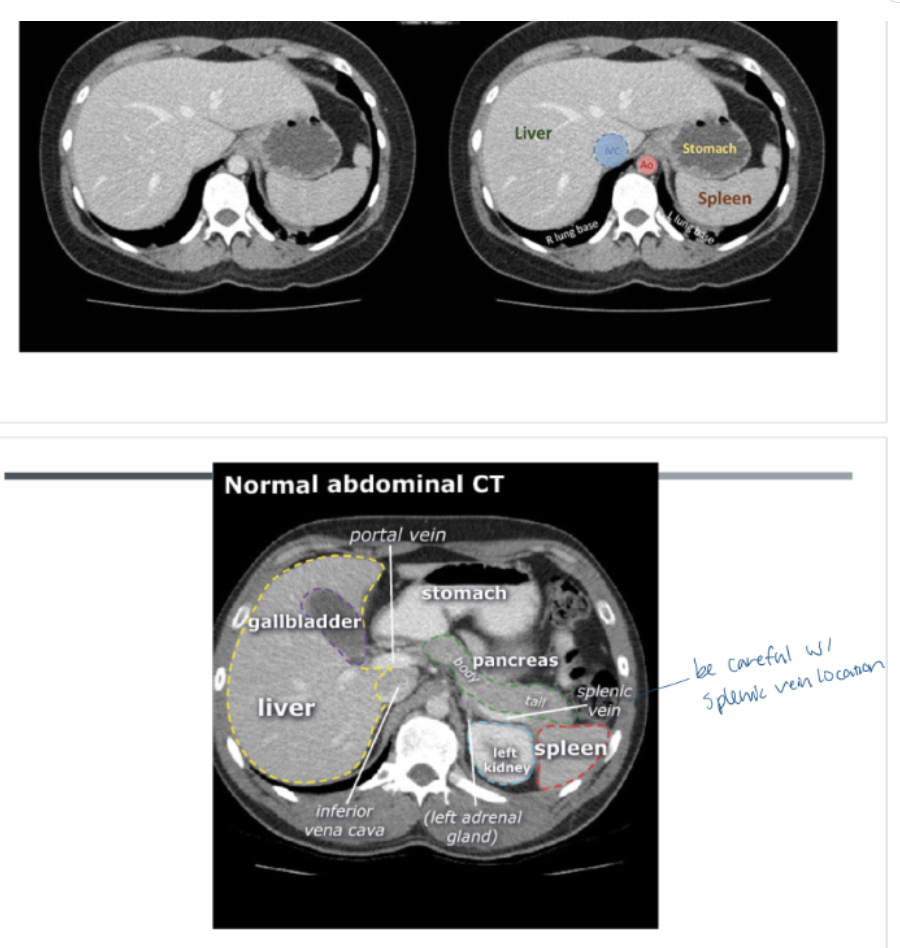

15

Q

Orientation:

A

• patient is scanned in the SUPINE position.

• The patient’s right is on the viewer’s left, and the patient’s left is on the viewer’s right, which is a standard convention in medical imaging to maintain consistency.

• top of each image is the anterior (front)

• bottom is the posterior (back) part.